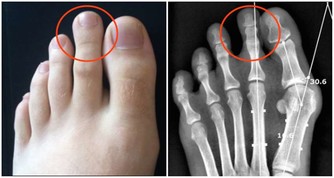

*****1.健康問題*****

過度勞累會對您的身心健康產生深遠的負面影響。無論是背痛,沮喪,心臟問題,肥胖症,還是經常生病,都要考慮工作是否是原因。您會知道過度勞累何時會影響您的健康,並且您將不得不決定是否值得這樣做。